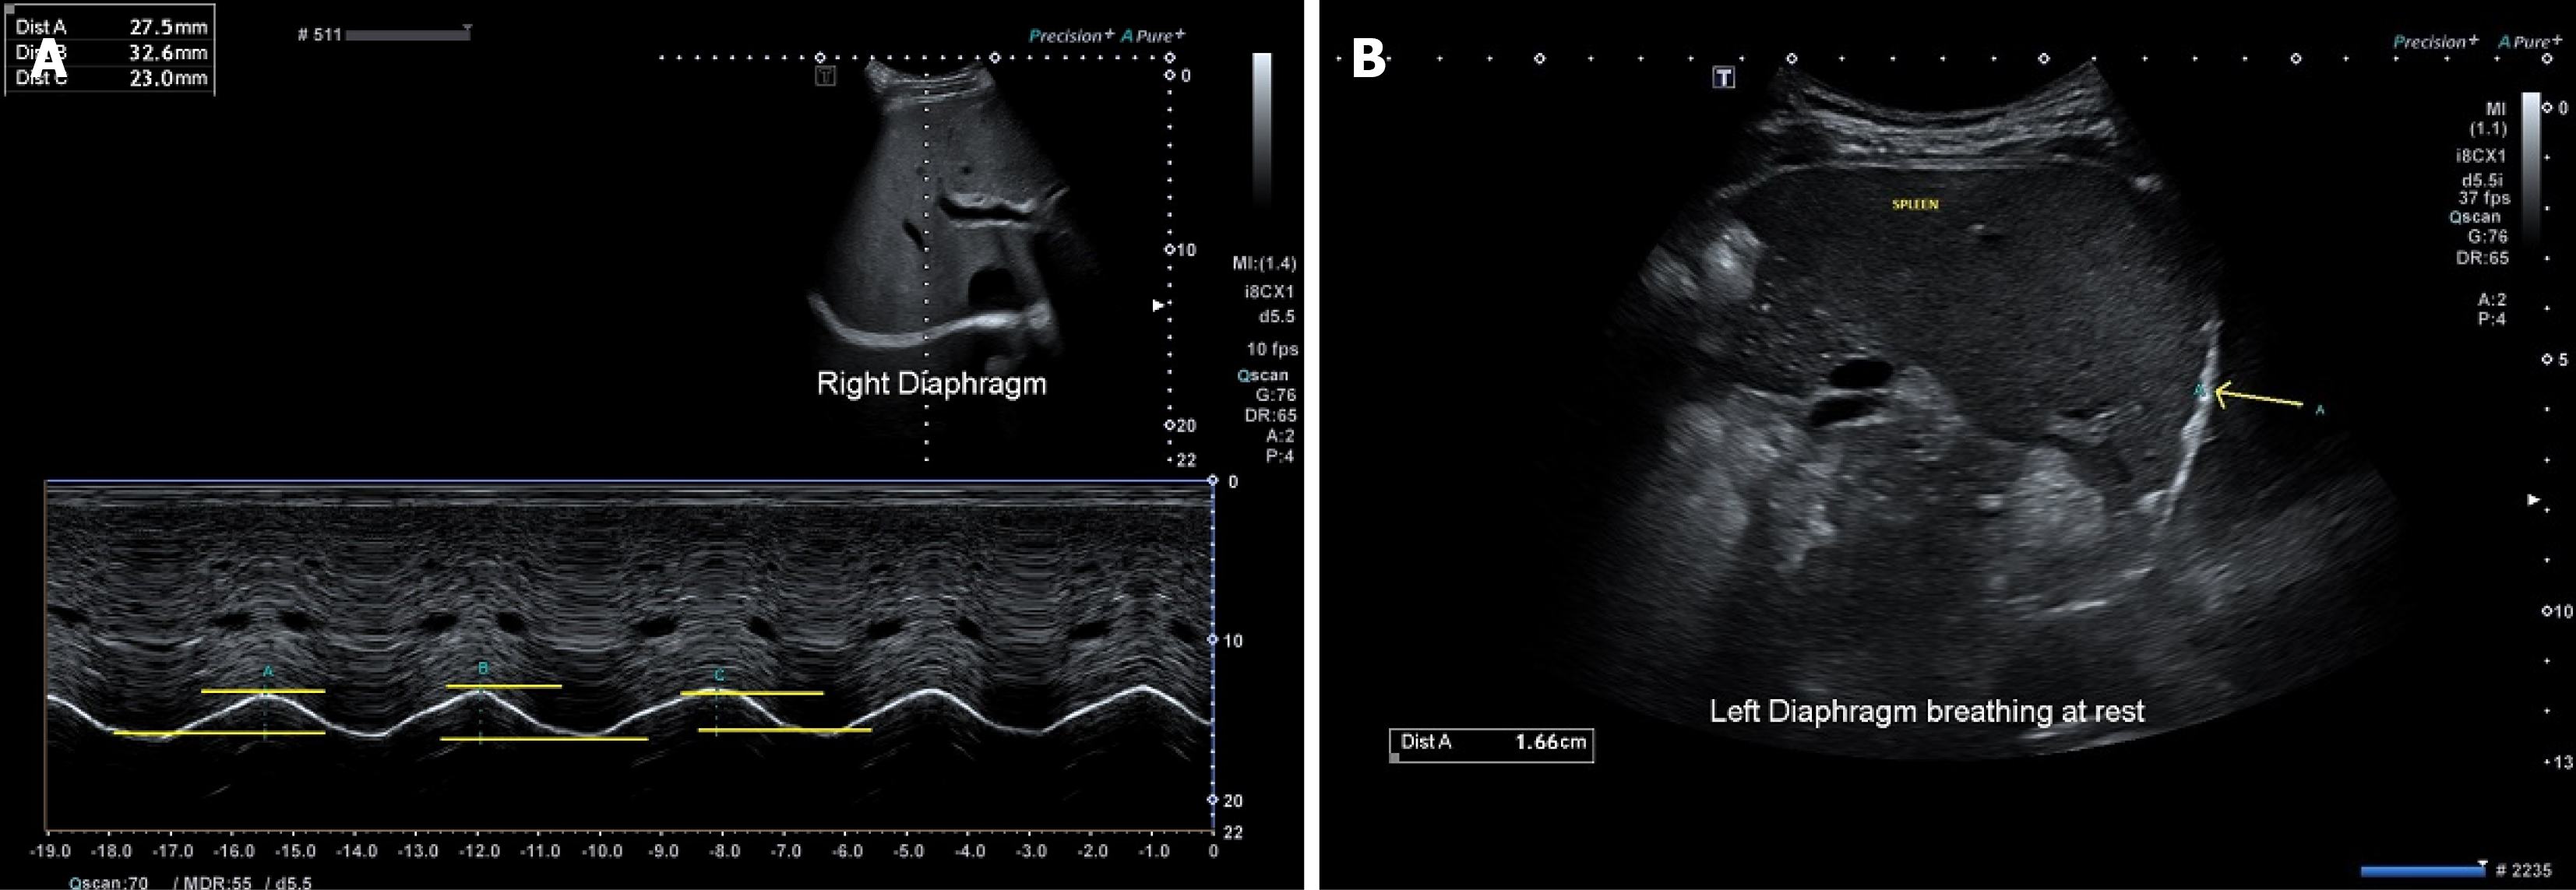

Figure 2 Excursion measurements for diaphragm.

A: Correct and incorrect methods of measurements for right diaphragm excursion. Measurements A: Correct position to put calipers; measurements B: Incorrect position to put calipers - on the exterior of the diaphragm; measurements C: Incorrect position to put calipers - on the interior of the diaphragm; B: Excursion measurements for left diaphragm at resting tidal breathing. Measurements A: Shows direction of diaphragmatic movement and position of calipers for measurement if M mode could not be used accurately due to the plane of diaphragmatic movement.